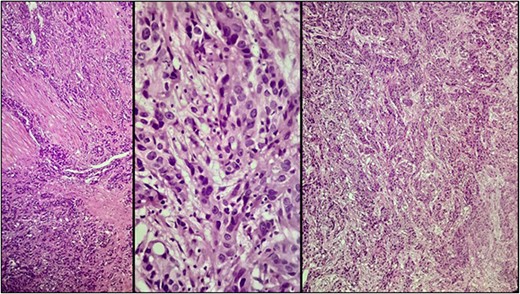

A 57-year-old male was referred to the urology department with hematuria 6 months before. Computed tomographic (CT) showed a mass in the bladder without any other significant results (Fig. 1). Endoscopic examination showed a solid lesion within a large diverticulum where biopsies were performed and the histopathology examination showed UC (invaded the lamina propria, pT1). A radical cystectomy with ileal conduit was performed with extended pelvic lymph node dissection. The histological study indicated the presence of a high-grade UC, which invaded the muscularis propria to the perivesical fat (Fig. 2) with neural and lymphovascular invasion (Fig. 3), but the metastases to pelvic or obturator lymph nodes were absent. After that, he received adjuvant chemotherapy (Paclitaxel), but he could not tolerate the side effects of the drug, which led to the cessation of treatment after only two doses. Two months later, he complained of swelling on the left cheek (Fig. 4) with pain in the left shoulder. Positron emission tomography and CT (PET-CT) showed an unclear, heterogeneous mass that leaches into the skin and adipose tissue underneath it and the left masticatory muscle measuring 40 × 20 mm showing pathological metabolic activity (Fig. 5). In addition to the presence of osteolysis in the posterior arch of the left eighth rib with the formation of a tissue mass extending over 75 × 35 mm showing pathological metabolic activity. Surgical intervention was performed to remove the described masses, and the histological examination demonstrated the presence of UC. Then, he received chemotherapy (Paclitaxel, 6 doses), and unfortunately PET-CT showed a relapse which occurred 4 months later, where the eighth rib was removed and supraclavicular region. Then, he underwent immunotherapy (Nivolumab) and radiation therapy until his death 10 months after the first appearance of cheek metastasis. There was no recurrence in place of the removed mass on the cheek.

Microscopic examination showing neoplastic cells arranged in irregular nests invading the lamina propria and muscularis propria. Tumors cells showing nuclear pleomorphism, hyperchromasia, high N/C ratio with frequent mitotic figures.